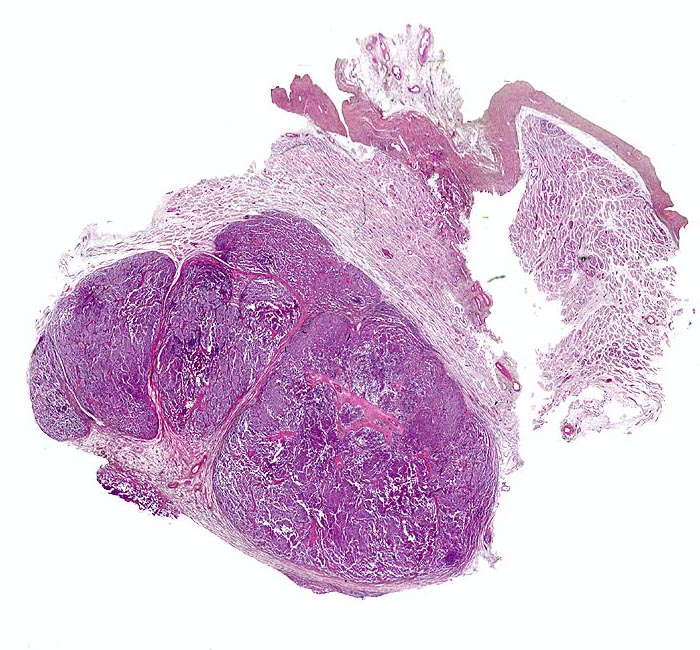

PathoPic ID 4677 - Seminom des Hodens

Seminom des Hodens

maligner Tumor

Hoden

Lobulierter zellreicher

Tumor mit scharfer Begrenzung.

Tunica albuginea.

Makroskopisch aus mehreren Knoten bestehender weisser Tumor von 2cm Durchmesser.

Der Patient suchte den Arzt wegen einer schmerzlosen Hodenvergrösserung auf.

Histologie

Scan

36

männlich